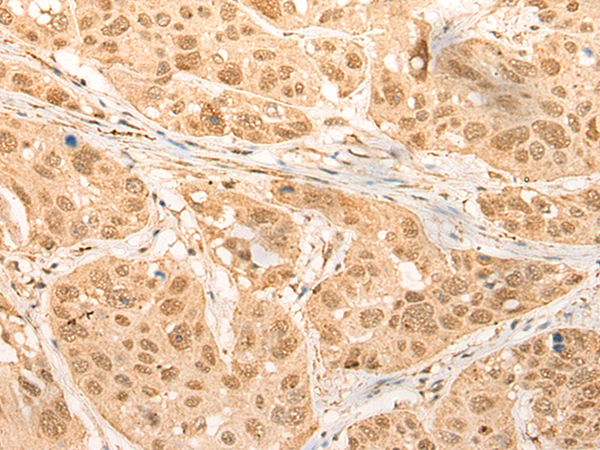

分类: 科研抗体货号: P09472别名:应用: IHC反应种属: Human, Mouse, Rat